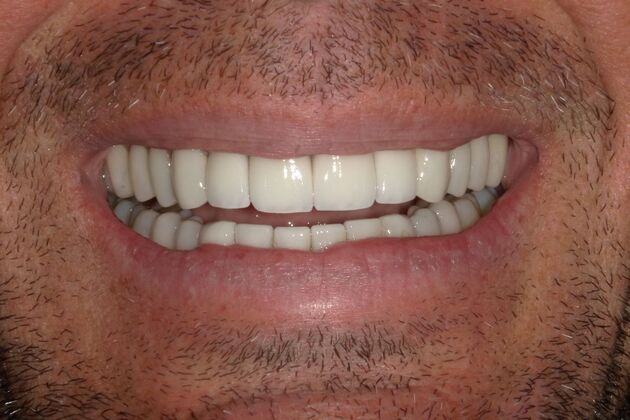

Full Mouth Reconstruction: Case 20

Description

This patient presented with old discolored crowns on his front two teeth, that were starting to break down. They had a metal substructure that he did not like the esthetics of. He is very happy with his new smile!